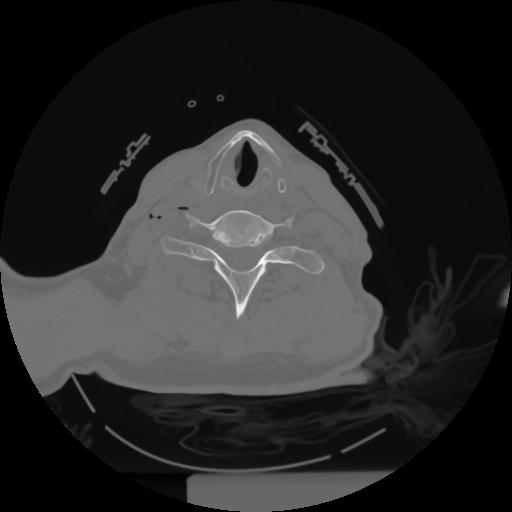

12 P.BLANDAS,,Vol,0.5,P.BLANDAS,,